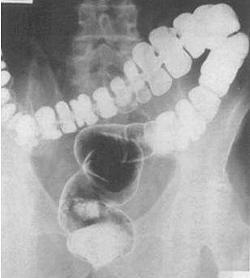

- Исследование транзита по толстой кишке: полная эвакуация радиоконтрастных меток указывает на запор с нормальным транзитом и согласуется с СРК с запорами.

Исследование с рентгеноконтрастными метками при медленнотранзитном запоре (инертная толстая кишка).